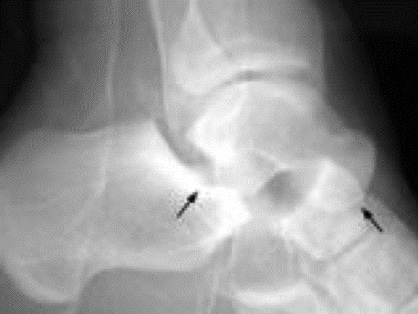

- There is disruption of the articulation of both the talocalcaneal and talonavicular joints

- Medial subtalar dislocations (85%)

- foot inverted, calcaneous displaced medially

- AP xray will show medially displaced calcaneous as above and lateral will show talar head superior to navicular bone

- Lateral subtalar dislocations (15%)

- Foot is everted, calcaneous is displaced lateral to the talus

- lateral xray will show talar head inferior to navicular